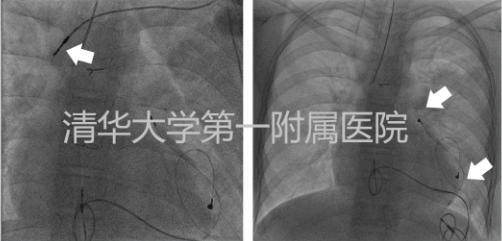

左图为拔出心房电极过程;右图为植入的心外膜心房及心室电极部位